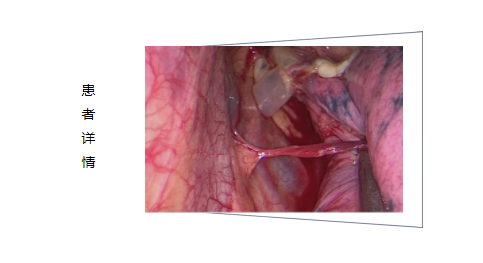

传统肺大泡切除术是单侧胸腔一个约8-10cm的切口,撑开胸腔,找到肺大泡,行肺大泡切除,手术创伤大,出血多,术后恢复慢,疼痛剧烈。目前,这样的手术,即便最微创的做法也需要在身上打2个孔才能做到。因患者年轻女性,综合各方面因素,程主任在微创手术的基础上再“微创”,把原来的3个孔“浓缩”成一个孔。单孔胸腔镜微创肺大泡切除,不撑开胸腔,出血少,创伤小,是治疗该病的首选方法。经过积极术前准备及和患者家属沟通,入院第三天,胸外科和麻醉科共同协作,施行单孔胸腔镜下肺大泡切除术。术中所见验证了术前的判断,多发肺大泡且有束带粘连。

手术仅在左侧胸壁上开了一个2cm的孔,在胸腔镜的引导下,将手术器械伸入胸腔内完成手术操作。术后2天拔除胸腔引流管,术后1周顺利出院。